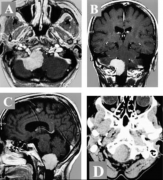

脑膜瘤3cm-4cm严重吗?脑膜瘤不开刀能活多久? 脑膜瘤(Meningiomas)是一种长在脑膜及脑膜间隙的的肿瘤,在颅内常见,80%以上脑膜瘤都是良性的肿瘤。典型的脑...

脑膜瘤 是脑膜的肿瘤,脑膜是覆盖大脑和脊髓的膜。较常见的是良性脑膜瘤或I级脑膜瘤,它们很小,不会像癌性肿瘤一样无限期地生长。非典型脑膜瘤w...

【较大脑膜瘤手术案例】故事源于一封字里行间充满了希望与感激的感谢信,写给INC之德国巴特朗菲教授,来自一个被较大脑膜瘤折磨导致肢体无力多年的...

【脑膜瘤德国治疗案例】原来3*4cm的较大 脑膜瘤 ,现在完全没有了。如今已手术后1年多了,没有复发,各项神经功能并无异常。相比于国内大多数脑膜瘤...